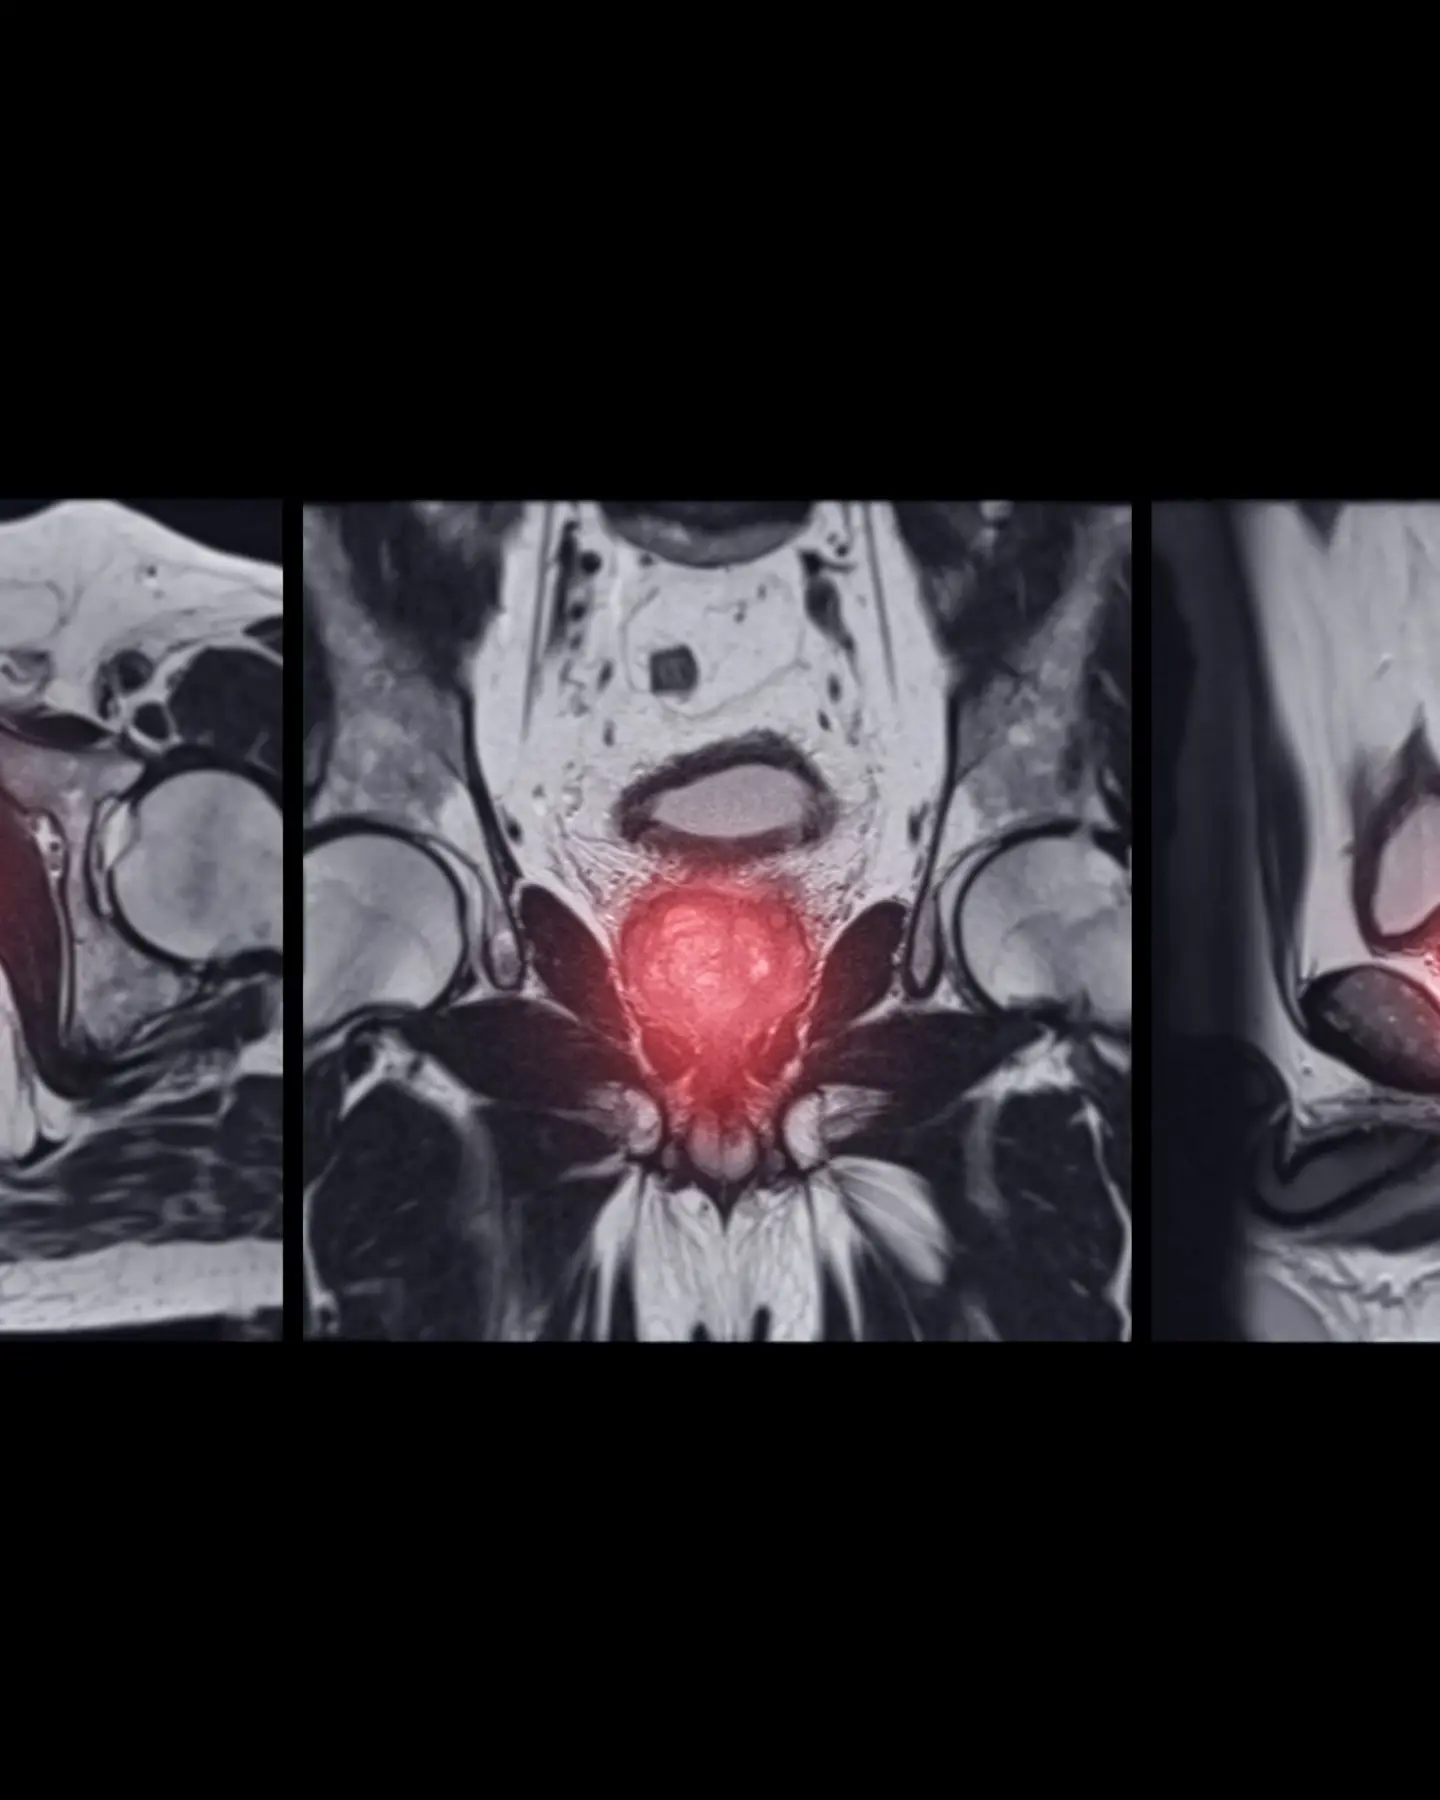

Prostate MRI scans

Fast, affordable access to private prostate MRI scans

Prostate cancer is the most common cancer in men, and about one in eight men will be diagnosed with the disease in their lifetime. A prostate MRI scan with Vista Health can detect prostate gland abnormalities, leading to the early diagnosis of conditions including cancer.

MRI stands for Magnetic Resonance Imaging, a way of taking pictures inside the body using magnetic fields and radio waves. A private MRI prostate scan uses the technique to focus on the prostate gland and the surrounding structures. It’s a safe, painless and non-invasive procedure.

Prostate MRI is used for the detection, evaluation and diagnosis of cancer and other conditions. Unlike X-rays and CT scans, MRI prostate doesn’t expose the patient to radiation.